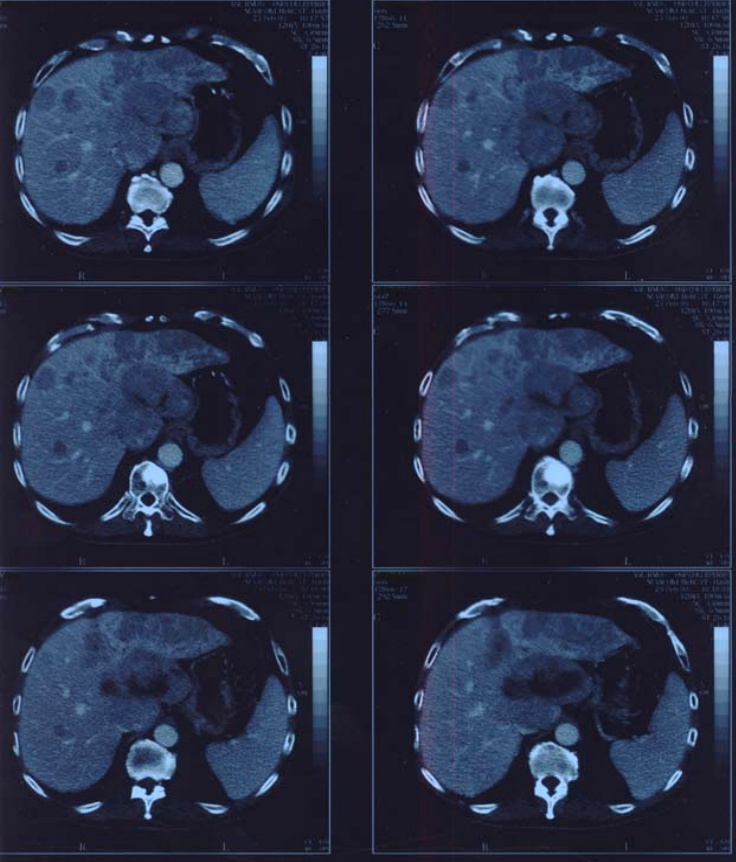

Figure1